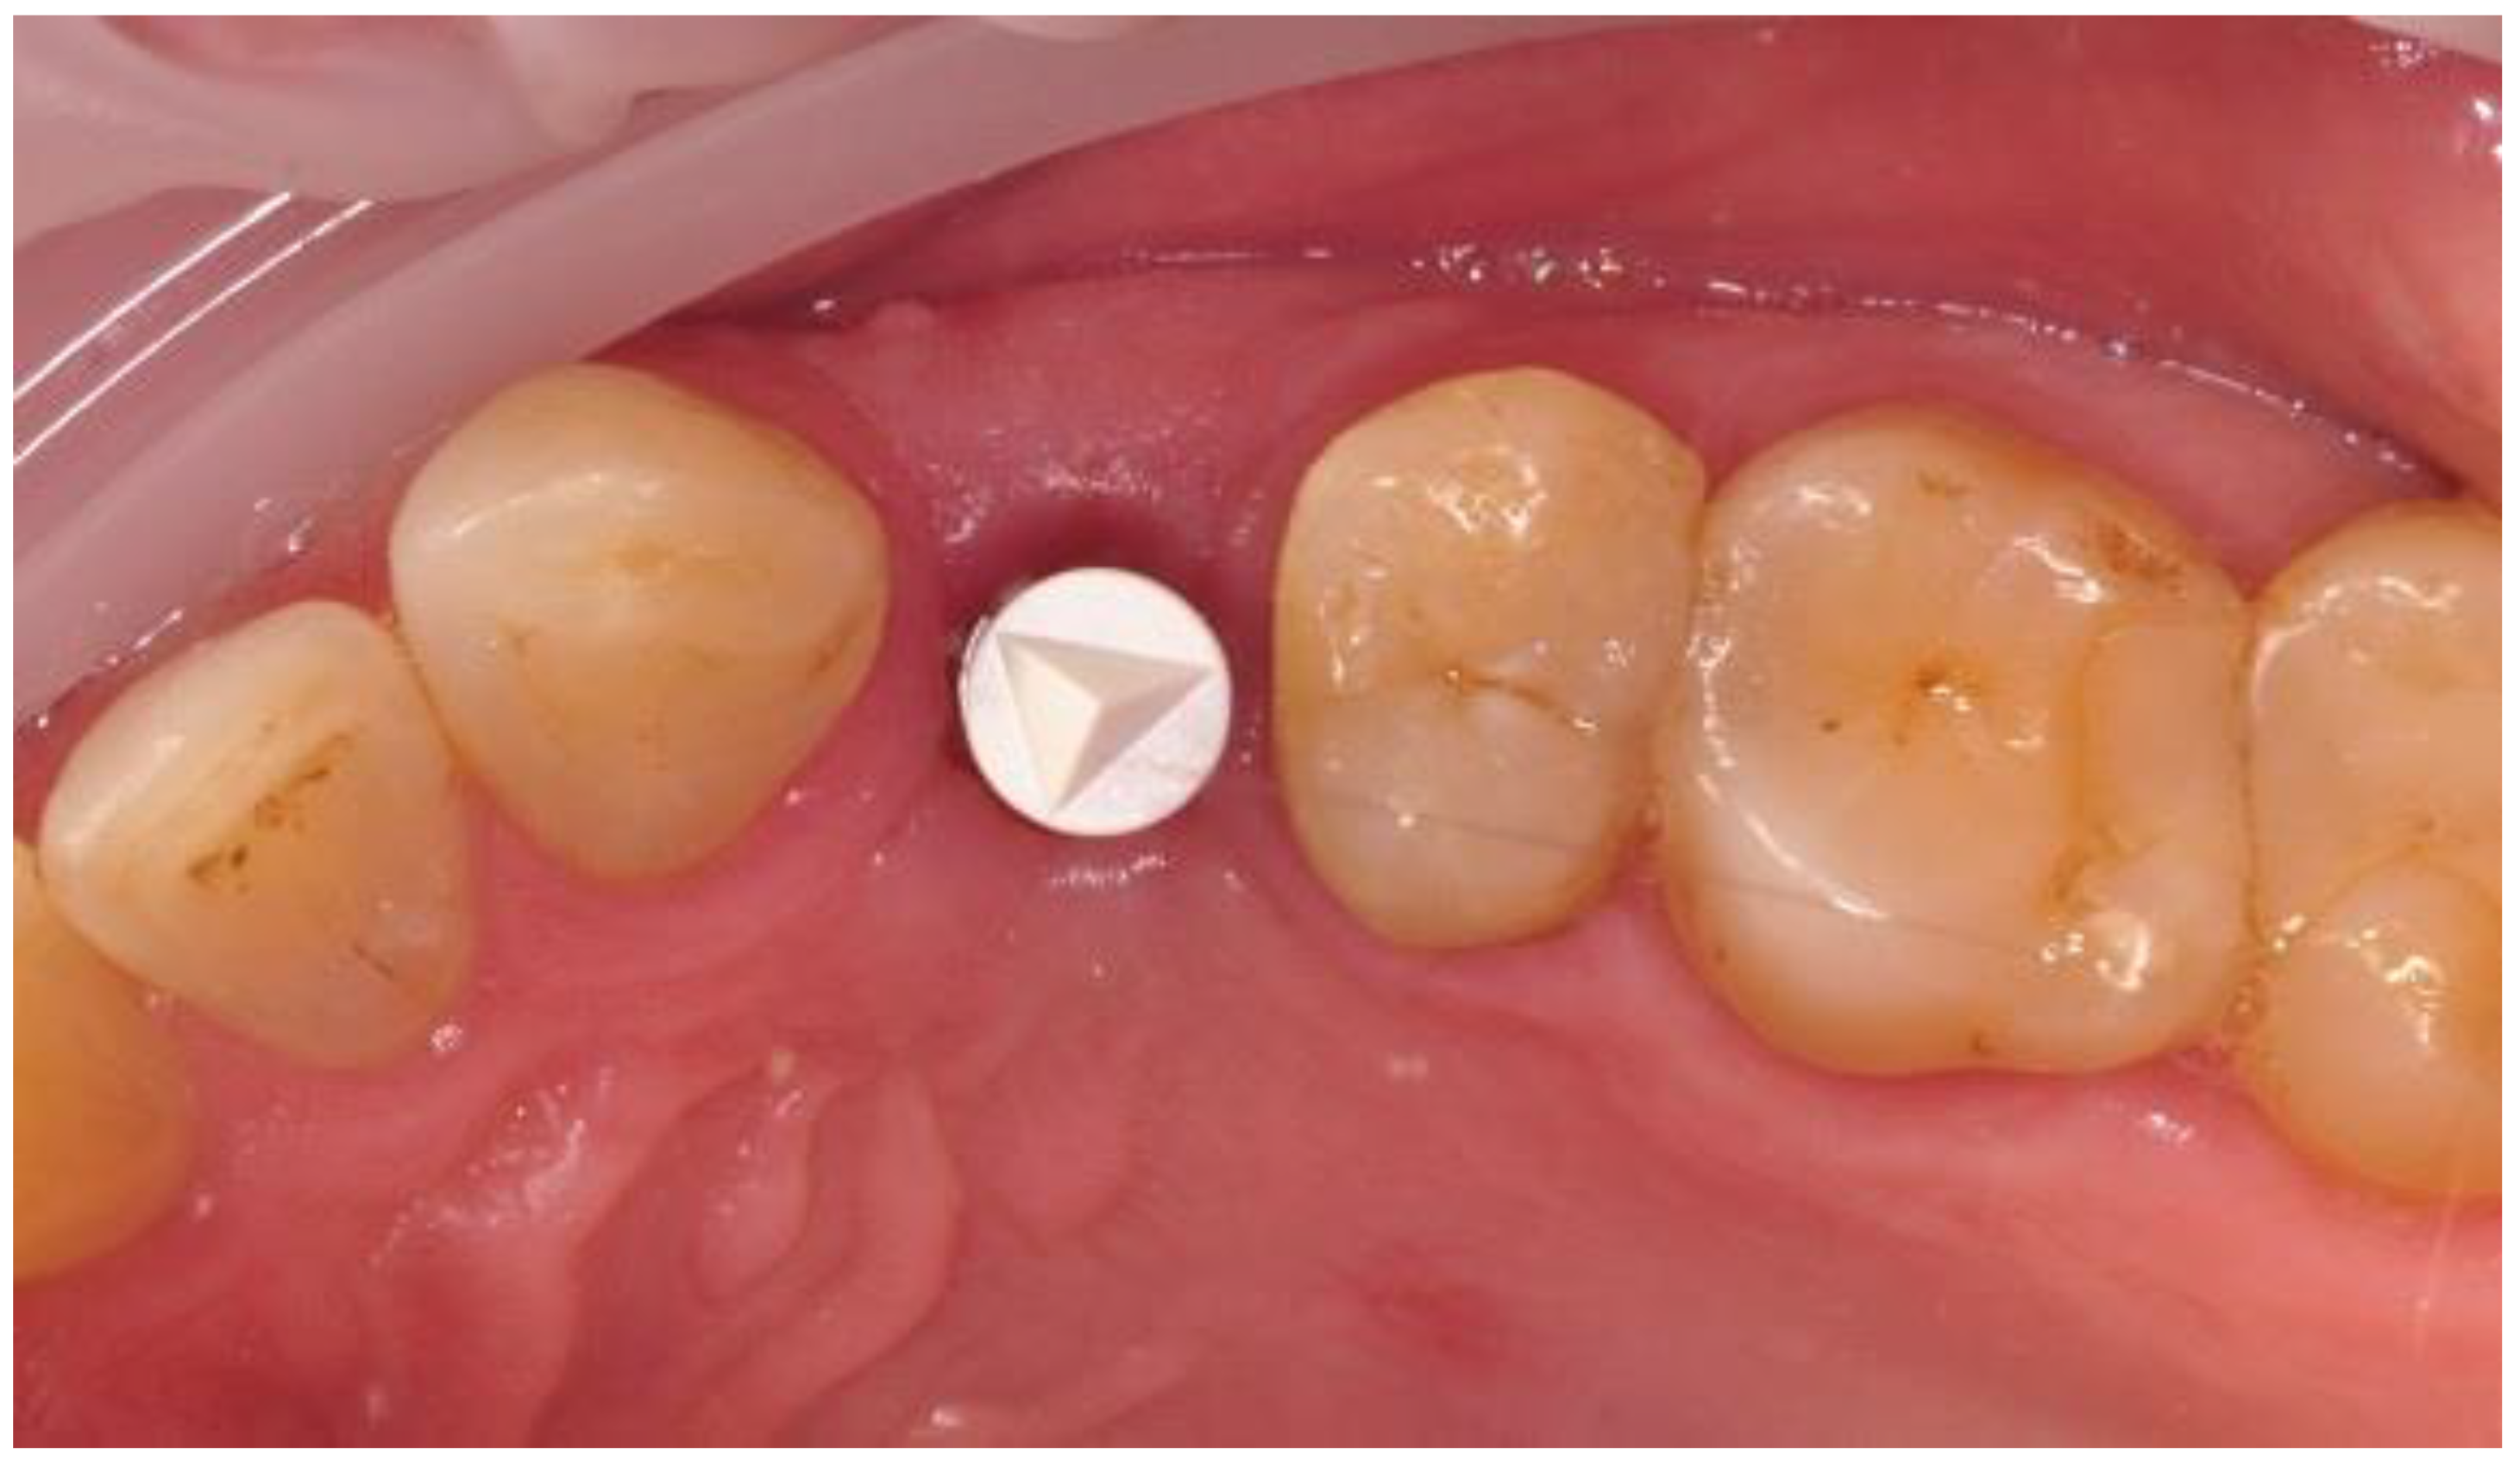

- Four weeks after the implantation: intraoral scan, screw-retained prosthetic, RVG;

2.5. Prosthetic Phase